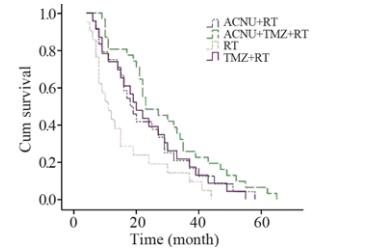

采用SPSS13.0进行分析,中位存活时间以 M(P25~P75)表示。采用Kaplan-Meier方法绘制生存 曲线,采用Logrank检验对四组生存曲线进行检 验,检验水准α=0.05。采用R×C表卡方检验对四组 患者的生存质量检验,检验水准α=0.05。 2 结果 2.1 临床疗效 2.1.1 生存时间分析

四组脑胶质瘤患者存活率 及中位生存时间见表1,生存曲线见图4。RT 组与 TMZ + RT 组和ACNU + RT 组的生存曲线比较, 差异有统计学意义(χL2=8.313和8.825,P=0.003和 0.012),即ACNU + RT组和TMZ + RT组的中位生 存时间长于RT 组;ACNU + RT 组和TMZ + RT组 生存曲线差异无统计学意义(χL2=0.047,P=0.915), 即ACNU + RT 组和TMZ + RT组生存时间差 异无统计学意义。ACNU+TMZ+RT分别与 ACNU+RT、TMZ+RT的生存曲线比较差异有统计 学意义(χL2=21.045和22.385,P=0.043和0.045),即 ACNU+TMZ+RT中位生存时间长于ACNU + RT 组 和TMZ + RT 组。

| 图4 四组脑胶质瘤患者生存曲线图Figure 4 Survival curves of glioma patients in four groups |